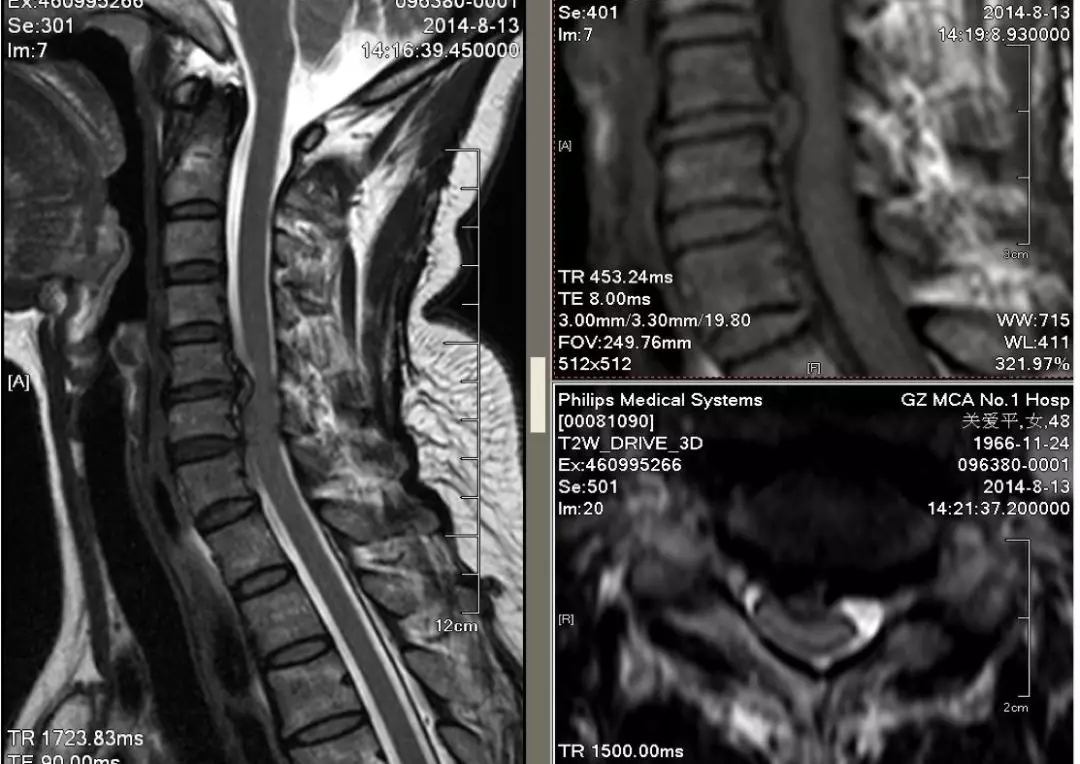

现在我们看到的是这是由于椎间盘突出引起的脊髓型颈椎病,我们可以看到椎间盘突出压迫了脊髓,脑脊液在这里不能通过,看到脊髓明显受压,脊髓没有明显的变性,神经根没有受压,这个类型的治疗原则是,可以保守治疗,但不宜做颈部牵引以及粗暴的手法操作。手术治疗方面,如果是前方致压物导致的以锥体束征为主,主要做的是前路手术,摘除椎间盘,骨刺,椎间融合,如果是以感觉障碍为主,伴有椎管狭窄的,可以做后路手术,包括椎管成形,椎管切除,如果是两者都有明显的症状,根据先后的顺序选择治疗方案,比如先有椎体束征的先做前路手术,观察三个月再选择做后路手术。